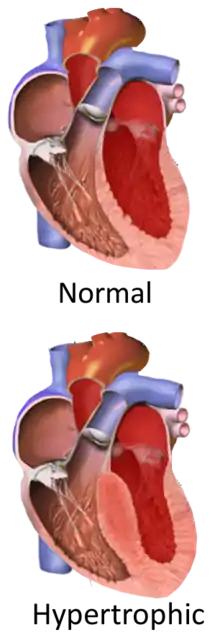

Hypertrophic cardiomyopathy (HCM) is a condition in which the heart becomes thickened without an obvious cause.[9] The parts of the heart most commonly affected are the interventricular septum and the ventricles.[10] This results in the heart being less able to pump blood effectively and also may cause electrical conduction problems.[3]

A diagnosis of hypertrophic cardiomyopathy is based upon a number of features of the disease process. While there is use of echocardiography, cardiac catheterization, or cardiac MRI in the diagnosis of the disease, other important considerations include ECG, genetic testing (although not primarily used for diagnosis),[26] and any family history of HCM or unexplained sudden death in otherwise healthy individuals. In about 60 to 70% of the cases, cardiac MRI shows thickening of more than 15 mm of the lower part of the ventricular septum. T1-weighted imaging may identify scarring of cardiac tissues while T2-weighted imaging may identify oedema and inflammation of cardiac tissue which is associated with acute clinical signs of chest pain and fainting episodes.[27]